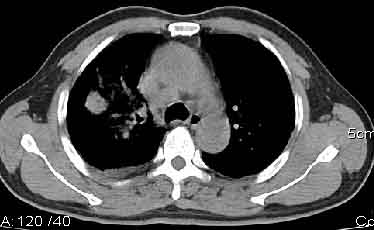

该病例我的诊断意见:右肺上叶周围型肺癌伴纵隔和右肺门淋巴结增大和右肺上叶阻塞性肺炎{病灶周围致密影以近肺门侧明显!}。右侧少量胸腔积液。

一. 1)症状有无发热及慢性过程.2)化验室检查?3)有无tb接触史?二.右肺上叶见片团状影,边界欠清,外侧方见一结节状软组织影,密度欠均匀,内可见低密度坏死区.周围强化明显,肺内见纤维索条影,局部胸膜增厚,但无明确胸膜凹陷.上叶支气管壁增厚,肺门及纵隔淋巴结增大.右侧胸腔少量积液.诊断意见:1右肺上叶慢性感染性疾病(肺tb?)伴肺门,纵隔淋巴结大.右胸少量积液.右肺上叶结节影多为tb球?2右肺上叶周围型肺ca伴肺门,纵隔淋巴结转移待排.右肺上叶炎变(肺门及纵隔淋巴结压迫).右胸少量积液.等待随返结果.